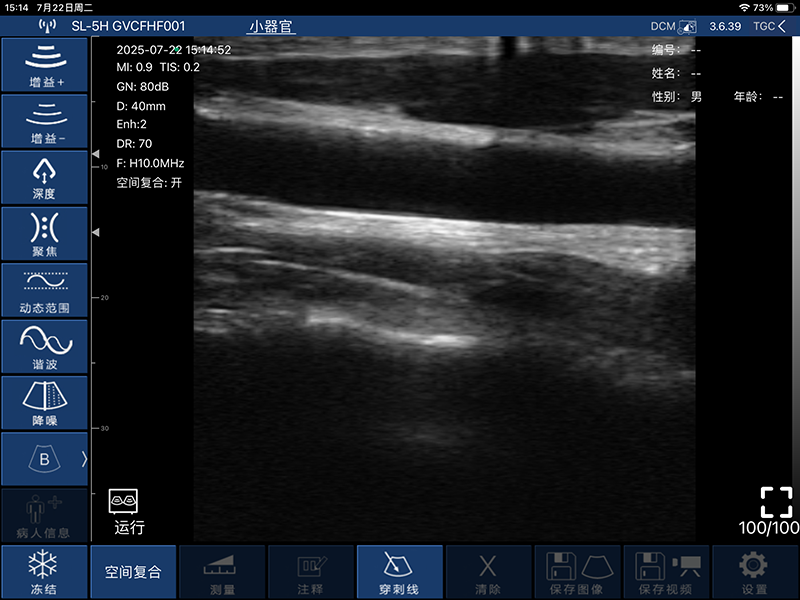

带指套探头的掌上彩超,小小的掌超主机放在口袋可随处走,手指套着探头即可完成打图成像,让手不再需要握着探头而可解放出来还能拿其他东西,特别适合术中等应用

- 扫描方式:电子阵列扫描

- 探头频率:7.5/10MHz

- 扫描宽度:25mm

- 扫描深度:10/20/30/40mm,可调

- 图像调节:增益、焦点、反相脉冲谐波、降噪

- 穿刺辅助功能:平面内穿刺引导线功能,平面外穿刺引导与血管自动测量功能

- 探头与主机连接方式:wifi无线连接

- Wifi类型:802.11n/2.4G/5G双频450Mbps

- 图像帧频:18f/s